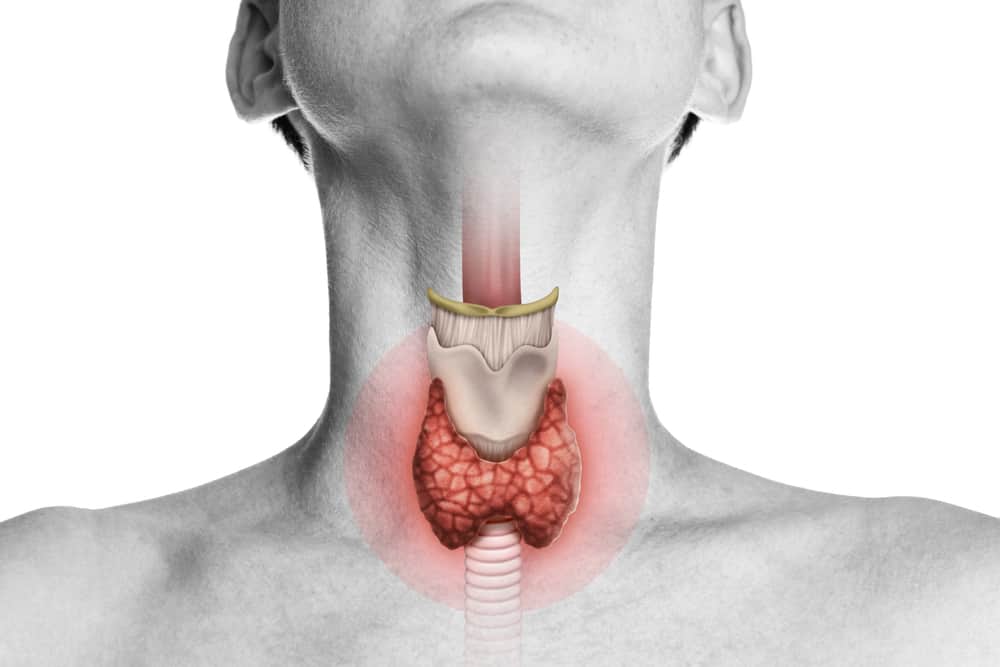

الغدة الموجودة في هذه الصورة هي الغدة الدرقية (Thyroid Gland) التي تفرز هرمونين يعرف أحدهما باسم الثيروكسين (thyroxin)، والآخر باسم الكالستونين (calcitonin)، هرمون الكالسيتونين وظيفته خفض نسبة الكالسيوم في الدم عند ارتفاعها.